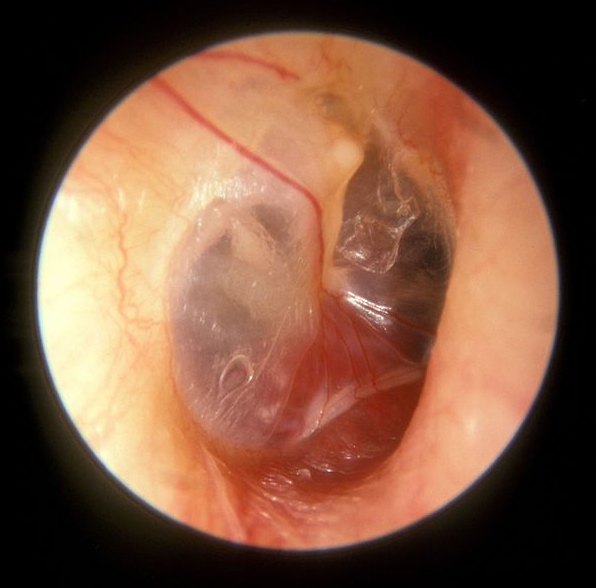

난소 낭종 파열에 대한 종합 가이드: 원인, 증상, 출혈, 종류 및 치료의 이해

난소 낭종 파열, 원인, 증상, 출혈, 유형 및 치료 옵션에 대해 알아보십시오. 이 상태를 효과적으로 관리하는 방법을 이해합니다. 난소 낭종에 대하여 “난소 낭종 파열”이라는 것에 대해 들어본 적이 있으신가요? 다소 복잡하게 들릴 수 있지만 걱정하지 마세요! 가능한 한 간단하게 설명해드리겠습니다. 이 글에서는 난소 낭종 파열의 원인, 증상, 출혈, 유형 및 치료 옵션에 대해 자세히 알아보겠습니다. … 더 읽기